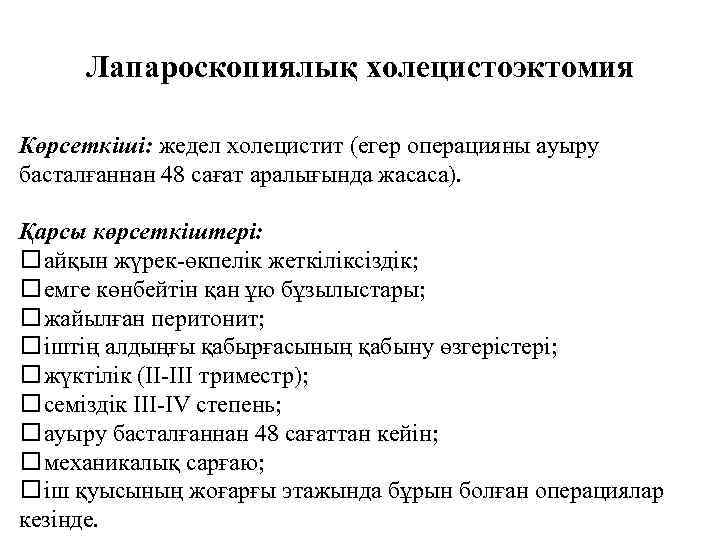

Лапароскопиялық холецистоэктомия Көрсеткіші: жедел холецистит (егер операцияны ауыру басталғаннан 48 сағат аралығында жасаса). Қарсы көрсеткіштері: айқын жүрек-өкпелік жеткіліксіздік; емге көнбейтін қан ұю бұзылыстары; жайылған перитонит; іштің алдыңғы қабырғасының қабыну өзгерістері; жүктілік (II-III триместр); семіздік III-IV степень; ауыру басталғаннан 48 сағаттан кейін; механикалық сарғаю; іш қуысының жоғарғы этажында бұрын болған операциялар кезінде.